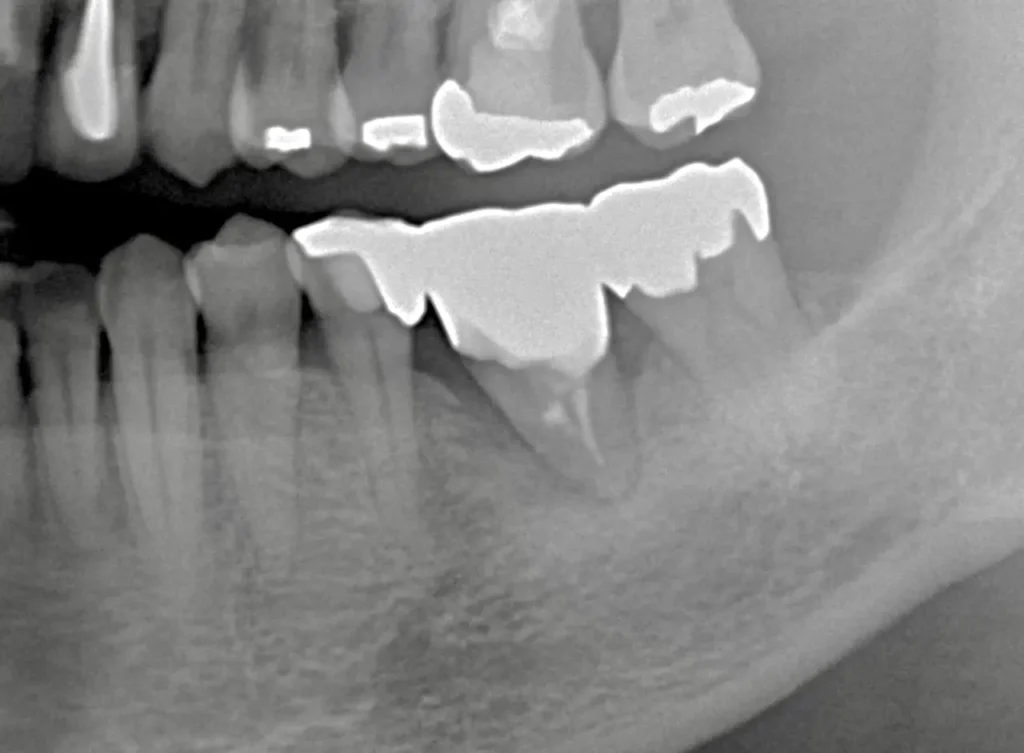

移植直後は支える骨が少ないです。

骨もしっかり増生してよく機能しています。